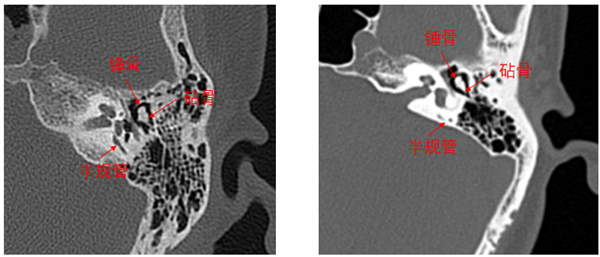

Precision 32精密断层能谱 CT完全由开普影像自主研发,拥有多项自主知识产权和多项专利。作为开普影像第一款CT旗舰产品,Precision 32CT拥有精密断层扫描专利技术PAxial——采用创新的扫描方式增加患者纵向采样,结合精密的重建算法,从数据采样和图像重建两个领域共同实现纵向超高分辨率图像重建,显著提高细微病变的检出率。全球发明专利精密断层扫描技术PAxial使Precision 32CT能得到仅0.275mm的业内超精细图像,在内耳成像和肺小结节探查等应用中有明显优势,全面助力精准诊断。比如,内耳成像领域除了能看清听小骨及耳蜗等内耳结构外,甚至连内耳各结构之间的关系都清晰可见。

Precision 32CT0.275mm精密内耳图像?普通CT0.5mm薄层内耳图像